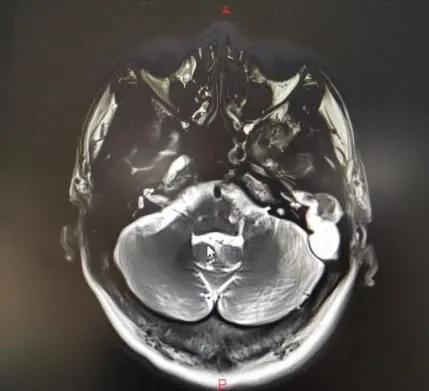

当地医院骨科将武先生诊断为颈椎病,后来又辗转几家医院仍无法确定病因……后来武先生住进郑州市中心医院神经外科,头颅MRI显示:左侧颞叶脑脓肿、中耳乳突炎。原来是因剧烈头痛再发“颅内感染”。

李玉杰主任认为,这是一例巨大“中耳胆脂瘤”破坏周围骨质后,蔓延至颅内引发的严重颅内外并发症。病根在中耳,必须尽快手术!

病因找到了,然而手术却是个难题!术前患者因中耳胆脂瘤导致的周围骨质破坏先后引起乙状窦血栓性静脉炎、硬脑膜缺损、脑膜炎、脑脓肿、迷路炎、面肌痉挛等多种颅内、外并发症,手术过程存在着巨大的风险,手术难度大,风险极高!

术中见硬脑膜骨质缺损最大处达到6平方厘米!围绕血管、面神经的病灶清理惊险迭起!稍有不慎就可能引发大出血、面神经损伤致永久性面瘫!清除病灶后的脑脊液漏修补及侧颅底重建过程更是精细而复杂!